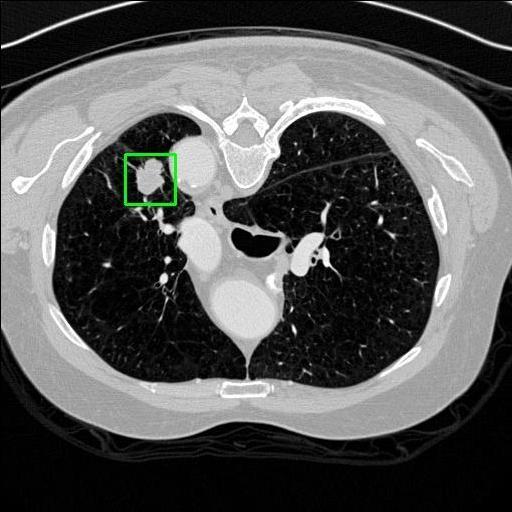

We developed an AI-based system using deep learning models for analyzing lung CT scans to detect and classify pulmonary nodules. We chose the YOLOv11 architecture for its enhanced object detection capability and adapted it specifically for medical imaging, incorporating pixel-level precision and severity classification.

Classification into three severity levels with colored bounding boxes.

Distinguishing between similar-looking benign and malignant nodules posed classification difficulty.

Designed a severity classification system that categorizes nodules into null, moderate, and severe using colored bounding boxes, assisting in rapid clinical decision-making.